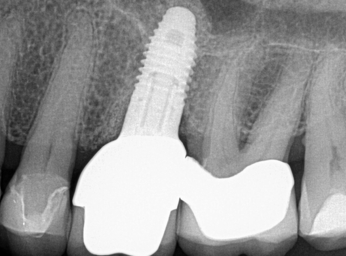

(31.) Single anterior custom abutment workflow.

Figure 31

(32.) Single anterior custom abutment workflow.

Figure 32

Following the recommendations of Yi, the transmucosal portion of the prosthetic connections should be flat or concave in profile diverging no more that 30 degrees from the long axis of the implants.19 Standard abutment profiles which are flat or convex in profiles are good examples to follow (Figure 19). Following Yi's recommendations individual posterior custom abutments with narrow implants should have flat or concave transmucosal profiles like a standard implant abutment with convex intaglio shapes like pontics that are cleanable with dental floss19 (Figure 20 through Figure 28).

Individual anterior custom abutments should have straight or concave transmucosal profiles extending to the desired gingival line at the FMG (Figure 29 through Figure 35).